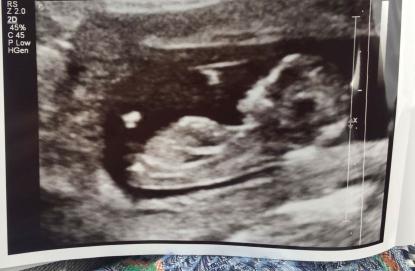

These pics are from 12 weeks 2 days . Im thinking girl but im not an expert. Would live some guesses please x Attachment 35635

Leaning boy from first pic - looks slightly angled to me

I think Boy too

Slight boy guess from me